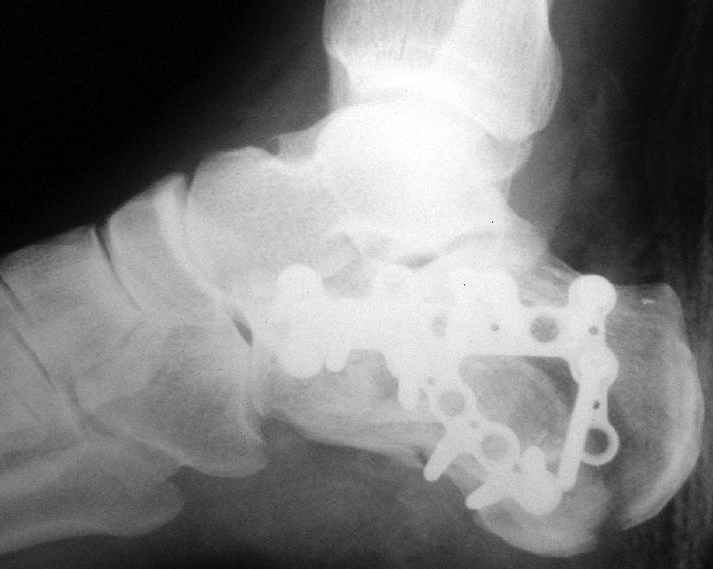

В/суставные переломы пяточной кости у молодых являются показанием к оперативной коррекции, Большой материал накоплен у д-ра Дрягина (Челябинск). В нашем отделении предпочтение отдаем открытой репозиции, при наличии выраженного отека, фликтен и т.д.

Накладываем спицевой дистрактор, позволяющий выхаживать м/ткани и одновременно устранять захождение отломков.

Окончательная фиксация спицами, пяточными пластинами (5) , в последнее время стали применять крючковидные пластины (ДЕОСТ) (6,6a).

представляю снимки пациента с переломом пяточной кости. послеоперационный снимок этапный - по снятии швов спицы удаляю и наладываю циркулярную гипсовую повязку. к сожалению снимки с удаленной скобой представить не могу но поверьте на слово - консолидация полная, коррекция стойкая.

при планировании операции и ее исполнении выполнена костная аутопластика трансплантатом с гребня подвздошной кости причем трансплантат брался фрезой размером несколько болишим чем образованный в результате травмы дефект. скоба в данном случае обеспечивает компрессию между отломками-трансплантатом